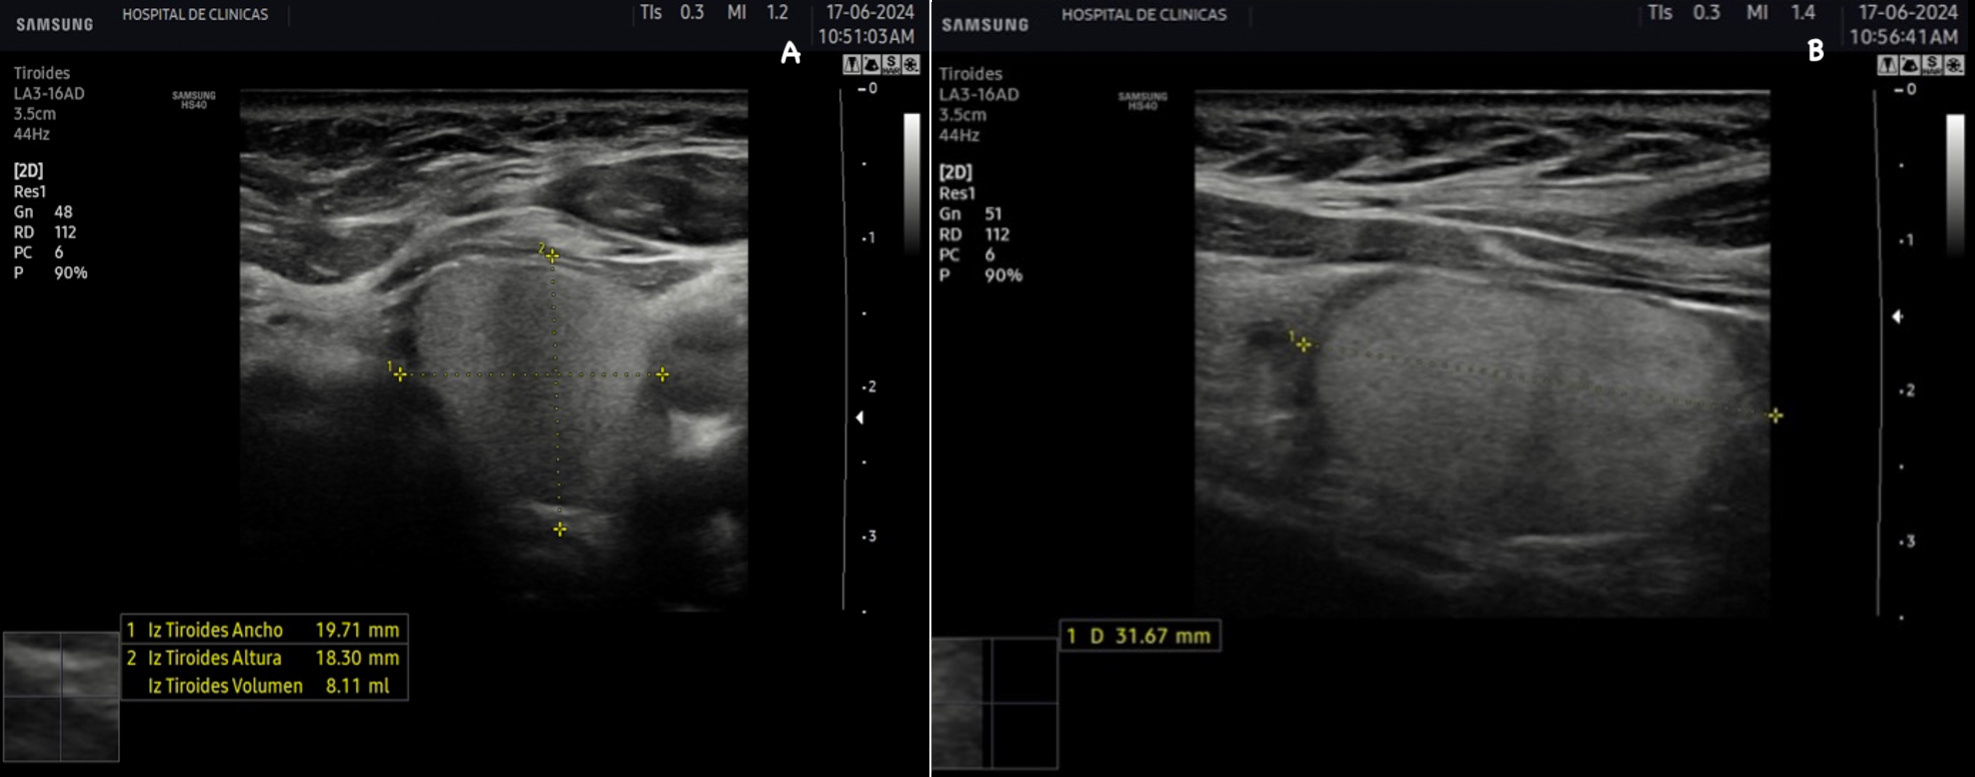

La tiroides de un adulto tiene un tamaño variable de aproximadamente 13 a 18 mm de ancho o transversal (T), 16 a 18 mm de profundidad o anteroposterior (AP) y 45 a 60 mm de largo o longitud (L), el istmo mide entre 2 a 6 mm de profundidad (AP). El volumen del lóbulo se calcula mediante la fórmula V (ml) = 0,479 × AP × T × L (cm). El número 0,479 o 0,524 en la fórmula es el factor de corrección para determinar el volumen de estructuras de una forma elipsoide, existen varias constantes y puede utilizarse cualquiera de ellas. El volumen de la tiroides es la suma de los volúmenes de ambos lóbulos. El volumen del istmo por ser pequeño, en general inferior a 10 mm no está incluido2. El volumen de una tiroides normal tanto en adultos como en niños es fuente de debate. La Organización Mundial de la Salud sugiere un volumen normal en hombres de 7,7 a 25 cm3 y en mujeres de 4,4 a 18 cm3(2). Depende de la edad y el área de superficie corporal de cada individuo2.

La ecogenicidad es media o alta cuando se compara respecto a los músculos pre tiroideos, tiene aspecto granular fino similar a las glándulas salivales y es isoecoica respecto a estas últimas. Cuanto más coloide y menos células haya en la glándula se produce mayor reflexión del sonido, por lo tanto, mayor ecogenicidad con respecto a los músculos pre tiroideos y demás tejidos como se observa en la figura 26.

La eco estructura es homogénea, los márgenes son regulares y presenta una cápsula ecogénica, su vascularización es escasa. El rango de referencia para una tiroides normal es de entre cinco y diez vasos visibles dentro de la exploración de cada lóbulo valorado con Doppler color2. Se ha descripto que hasta un 50% de los individuos presentan lóbulo piramidal (Figura 3a y 3b). Este sector, en general, es similar en ecogenicidad, homogeneidad y vascularización al istmo y los lóbulos. En la superficie posterior de los lóbulos tiroideos, especialmente en el segmento inferior, puede visualizarse el tubérculo de Zuckerkandl, un ejemplo de este se puede observar en la figura 4a y 4b. Este es un tabique hiperecogénico fibroso que a menudo genera sombra posterior. Se forma por la extensión del tejido tiroideo de las áreas laterales de los lóbulos hacia el sector posterior, y a menudo exhibe una disminución de la ecogenicidad detrás del mismo. Este proceso puede imitar una lesión tiroidea o paratiroidea y causar dificultades en la interpretación2.

Figura 2: Corte transversal de la tiroides normal, se señalan con las

flechas distintas estructuras.